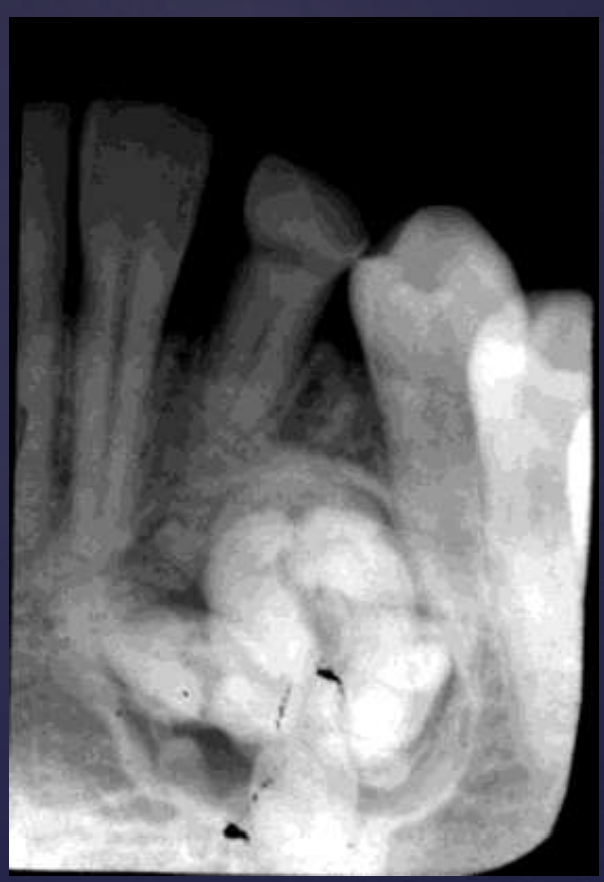

COMPLEX odontomas

Well defined, corticated

Radiolucent band/soft tissue capsule inside the cortical border

Internal content is largely radiopaque- made of irregular mass of calcified tissue

Maybe be associated with unerupted tooth

Possible displacement of teeth (30, 29)

Compound –Complex Odontoma

Well defined

Mixed density, corticated

Combination of amorphous radiopaque mass and tooth like structures

Osseous expansion

Thinning of cortices

Displacement of teeth, unerupted tooth